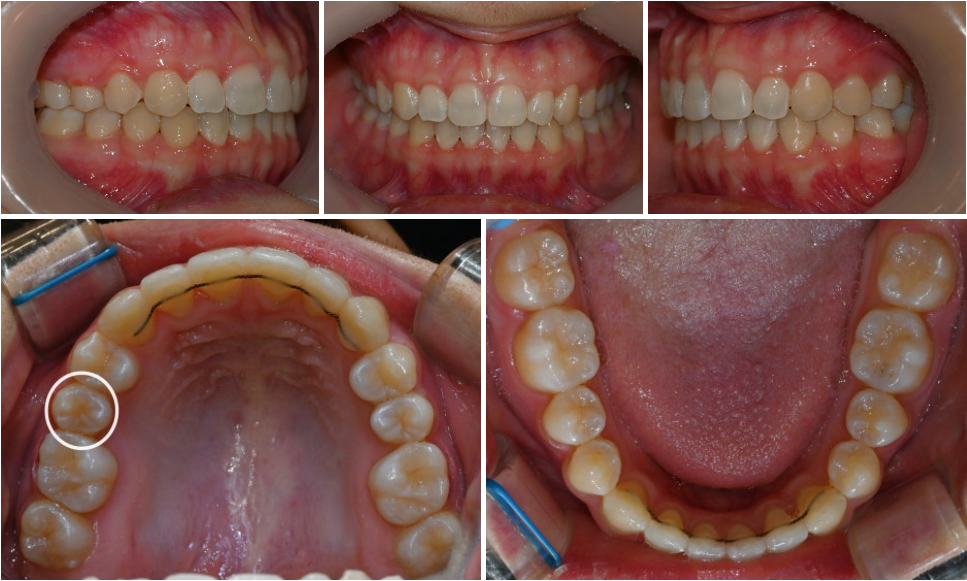

25.01.12

치료 후에는 어금니 뿐만 아니라 앞니 관계까지

좋아진 모습으로, 정상교합을 되찾을 수 있었습니다.

유치 잔존에 의한 이소맹출 같은 경우는

유치를 적절한 시점에 발치해주면

쉽게 해결 가능한 문제입니다.

단, 발견이 늦어 매복되어 버린다면

교정장치를 통한 견인 작업으로

영구치를 올바른 위치에 돌려놓아야 됩니다.